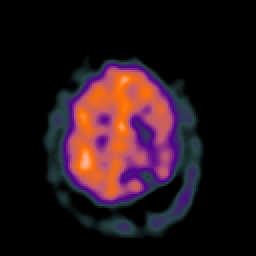

SPECT TC Study #2 -- Slice #41

[Home][Help][Clinical][Tour 1][Tour 2][Tour 3] Slice 41